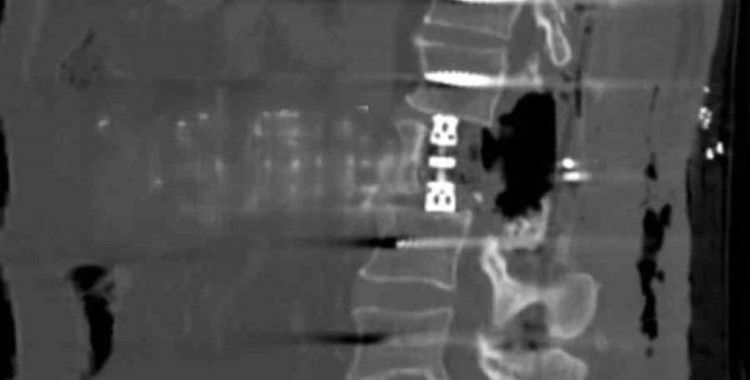

Bayburt Devlet Hastanesine belli başlı şikayetlerle başvuran hastaya korpektomi ameliyatı yapılarak, hastanın tümörleri temizlendi. Hastanın bel omurundaki enfeksiyon temizlendikten sonra kafes ve enstrüman sistemi ile sabitleme yapıldı. Beyin ve Sinir Cerrahisi Uzmanları Op.Dr Aziz Kaan Erçandırlı ve Op.Dr Ali Emre Özer tarafından yapılan operasyonla, hasta sağlığına kavuştu.